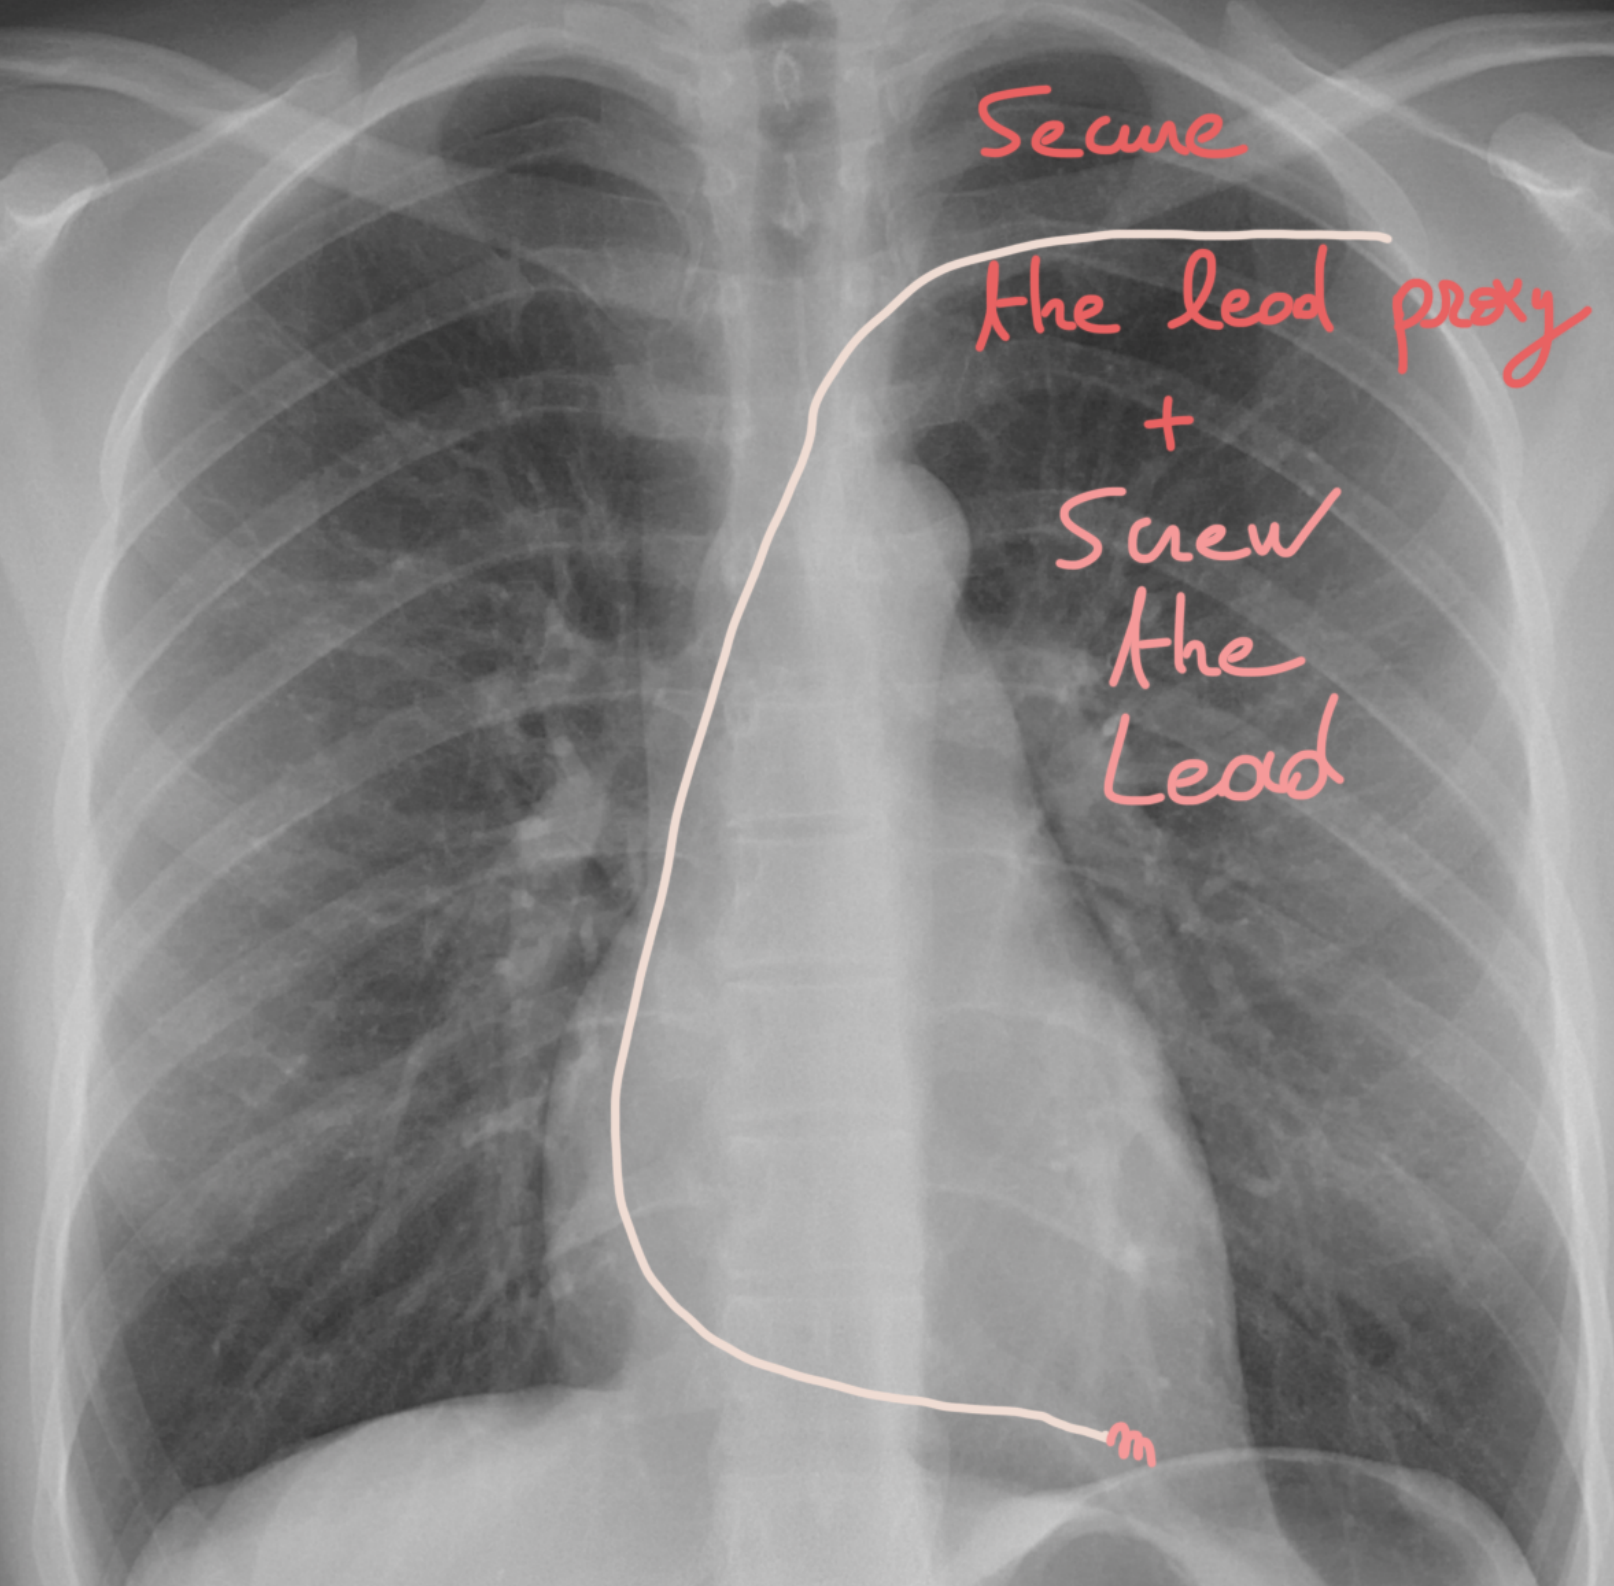

๐Ÿ”ฉ Step 19: Lock it in & test! ๐Ÿ“Š

If youโ€™re happy with the current of injury โœ…, you can now screw in your lead ๐Ÿช›.

๐Ÿ‘‰ Then check the key parameters:

Sensing ๐Ÿ‘‚โšก

Threshold ๐ŸŽฏ

Impedance ๐Ÿ“‰

If everything looks good ๐Ÿ‘, you can secure the lead proximally so it stays right where it belongs.

Think of it like anchoring your spaceship ๐Ÿš€ before take-off โ€” stable, safe, and ready to perform!